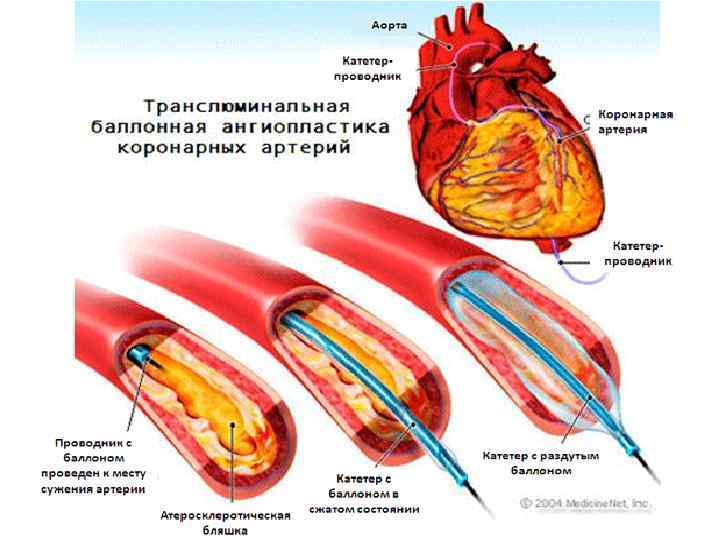

Теріішілік транслюминальды коронарлы ангиопластика: v Бағыттаушы катетер сан немесе қол артериясына қойылып, ішіндегі жіңішке металл түтікше бітелген коронарлы артерия аймағына тығылады. Түтікше басындағы шар, бітелген аймаққа келгенде үрленіп, бітелген артерия өзегін кеңейтеді. Содан кейін түтікше қантамыр ішінде қалады да, ал катетер мен шар алынып тасталады. v Нәтижесі: бітелген артерия өзегін ашады, қанайналым қалпына келеді және симптомдар жойылады. Бірақ атеросклероз процессін толық тоқтатпайды. Сол үшін науқас профилактикалық дәрілер ішуі тиіс. Сол үшін стенттау жиі қолданады. v Асқынуы: атеросклеротикалық түйіндердің қайта қантамыр өзегін бітеуі. Операция қайта жасауға тура келеді.

Теріішілік транслюминальды коронарлы ангиопластика: v Бағыттаушы катетер сан немесе қол артериясына қойылып, ішіндегі жіңішке металл түтікше бітелген коронарлы артерия аймағына тығылады. Түтікше басындағы шар, бітелген аймаққа келгенде үрленіп, бітелген артерия өзегін кеңейтеді. Содан кейін түтікше қантамыр ішінде қалады да, ал катетер мен шар алынып тасталады. v Нәтижесі: бітелген артерия өзегін ашады, қанайналым қалпына келеді және симптомдар жойылады. Бірақ атеросклероз процессін толық тоқтатпайды. Сол үшін науқас профилактикалық дәрілер ішуі тиіс. Сол үшін стенттау жиі қолданады. v Асқынуы: атеросклеротикалық түйіндердің қайта қантамыр өзегін бітеуі. Операция қайта жасауға тура келеді.

Операция рентгендік бақылаумен өтеді • Диагностика сатысында коронароангиография жүргізіледі, тарылу көлемін, орынын анықтау үшін • Доступ – сан артериясы • Арнайы катетер арқылы контрастты зат енгізіледі де, рентен түсіріледі • Катетер арқылы өткізгішті жібереді, ал өткізгіште баллонды стент орналасады

Операция рентгендік бақылаумен өтеді • Диагностика сатысында коронароангиография жүргізіледі, тарылу көлемін, орынын анықтау үшін • Доступ – сан артериясы • Арнайы катетер арқылы контрастты зат енгізіледі де, рентен түсіріледі • Катетер арқылы өткізгішті жібереді, ал өткізгіште баллонды стент орналасады